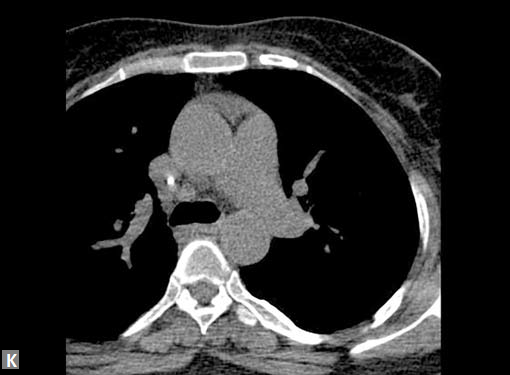

Connective tissue disease, hypertension and iatrogenic (Figs 19K to L) injury are the common causes for dissection. Radiologist not only establishes the diagnosis, also evaluates the extent of dissection, presence of thrombosis particularly in false lumen. In case of type A dissection, involvement of aortic root is determined. Relation of thrombosed lumen and ostia of coronary vessels, cephalad branches (Figs 19N, R to V) of aorta is determined. Most of the occasions membrane is demonstrated. Spiral nature of the membrane can be seen

Pericardial effusion may accompany type A dissection.

Hemopericardium is the dreaded complication of leaking

type A dissection (Figs 19S to V). The type B dissection can

Figs 19A to Y (A to C) Scannogram (A), plain (B) and contrast study (C) show partial anomalous pulmonary venous connection; (D to F) Heterotaxy; (G) Aortic occlusion; (H and I) Aortic stents; (J) Aortic dissection with ‘Benz’ sign due to second dissection within the true lumen; (K, L and M) Aortic dissection with thrombus in pseudolumen following catheter angiogram; (N) Aortic dissection involving common carotid arteries and subclavian artery; (O, P, Q and R) Aortic dissection with right renal artery arising from true lumen and left renal artery from false lumen; (S, T, U and V) Stanford B dissection with extension Y to iliac vessels; (W to Y) Aneurysmal dilation of ascending aorta